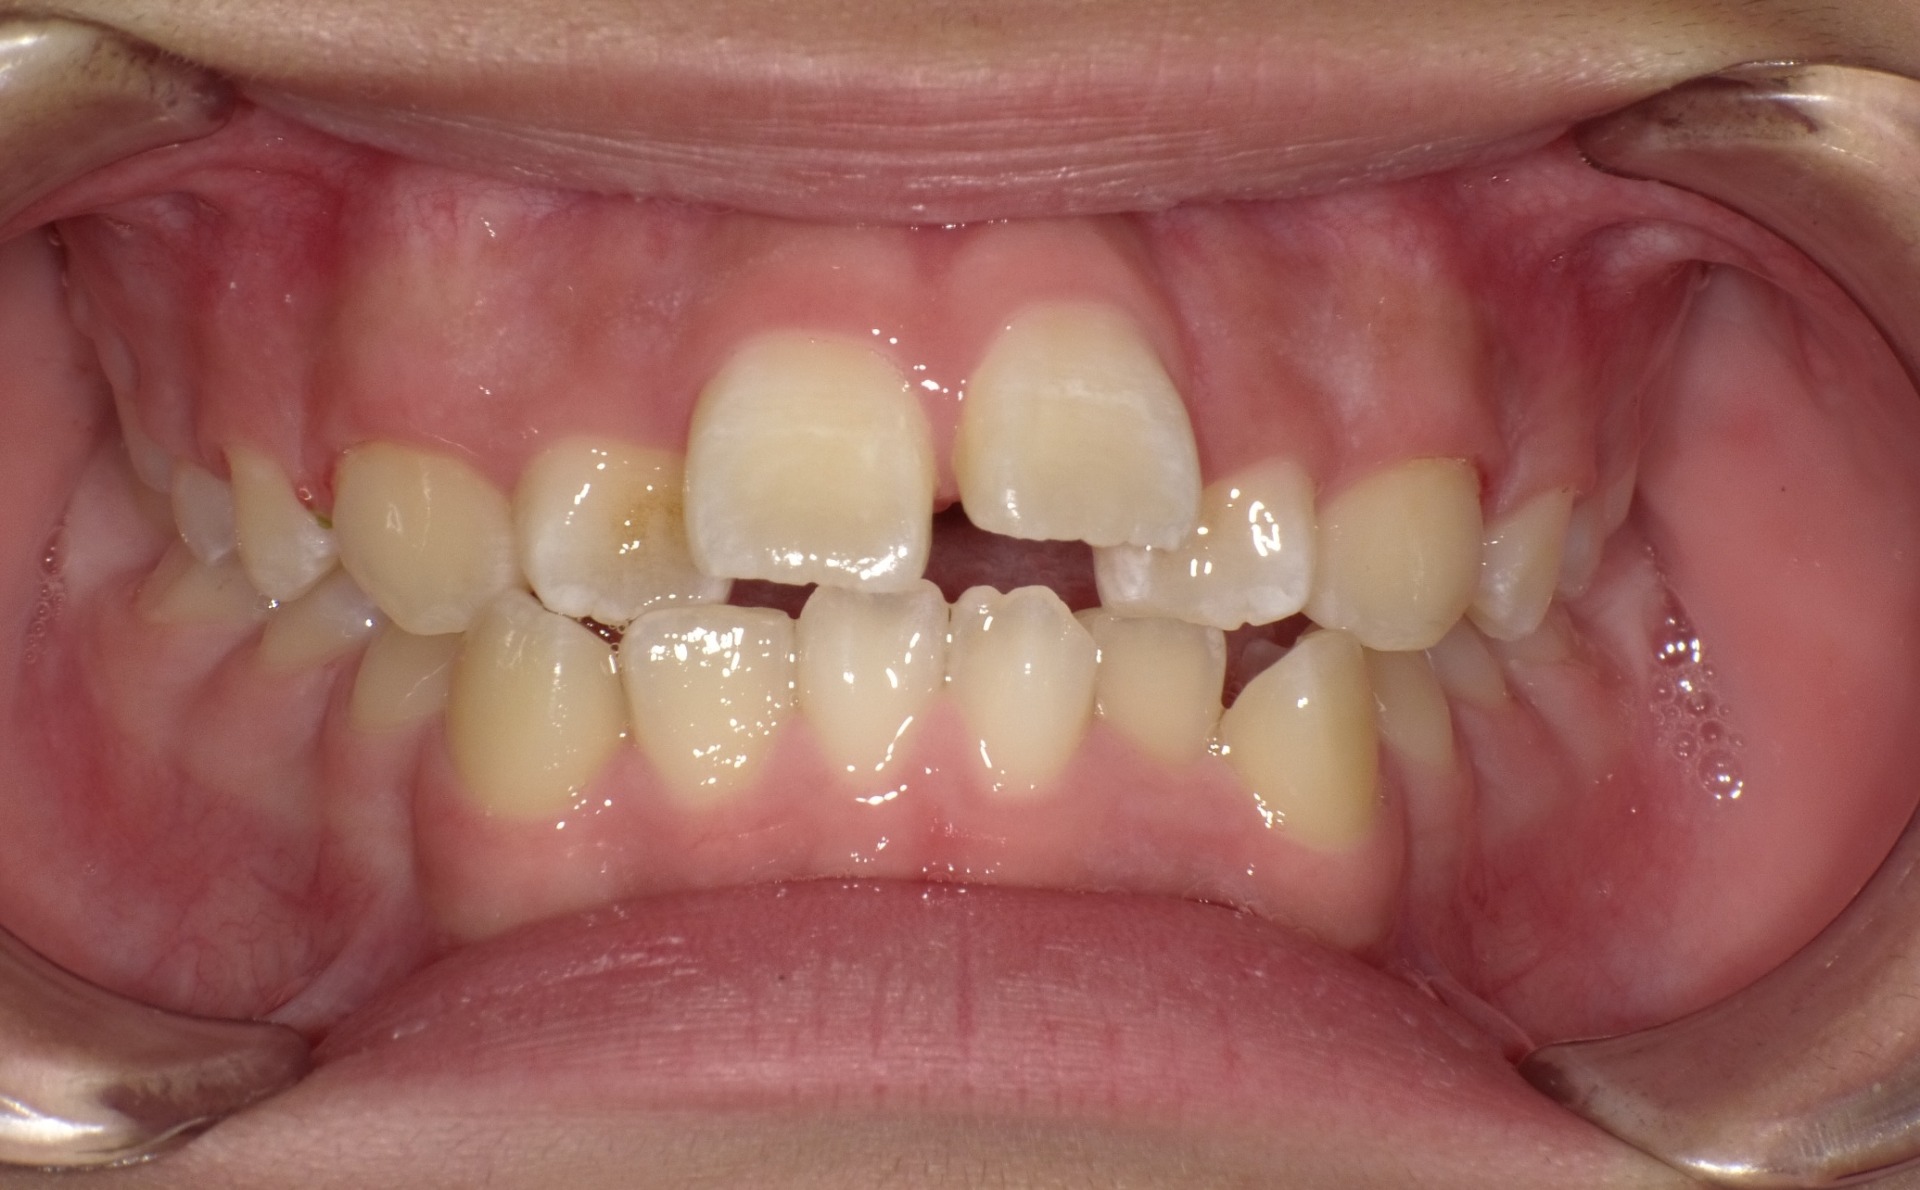

矯正前